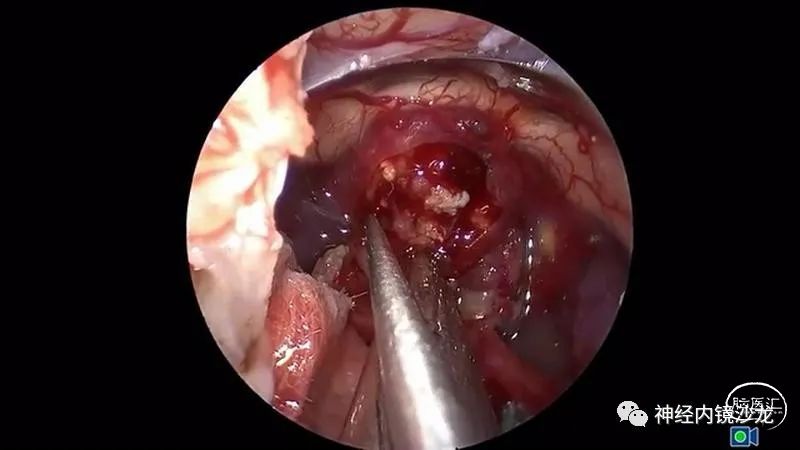

手术暴露充分术野,从蝶骨平台到斜坡,从眼眶到眼眶。切除大块钙化部分肿瘤后,我们找到肿瘤包膜和下丘脑、视觉通路之间的清晰的分离平面。切除结束时,发生了后交通动脉从大脑后动脉撕脱导致的动脉出血。采用单轴持夹器放置一个成角的动脉瘤夹,以夹闭损伤部位并保证供血动脉不狭窄。术后即刻和晚期磁共振成像和CTA检查显示肿瘤全切、无卒中、无假性动脉瘤形成。